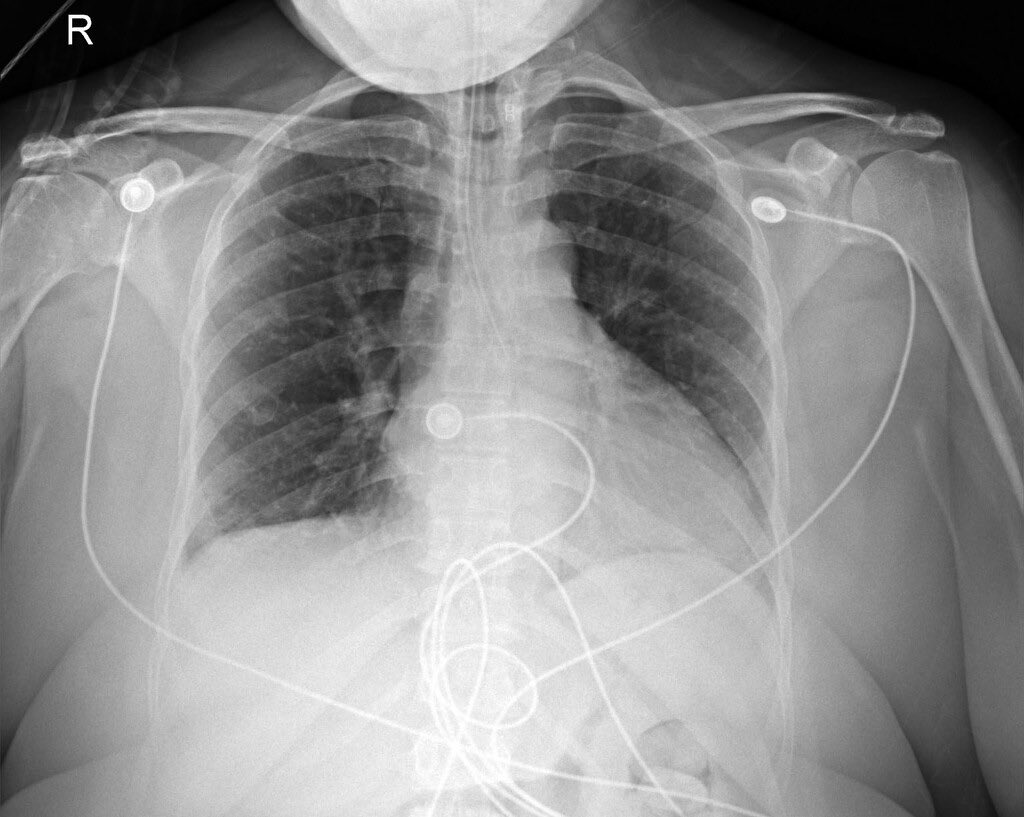

A patient presented with localized, acute, sharp pain in the outer thigh accompanied by numbness and tingling. Worsened when wearing jeans. What is the likely diagnosis? H/t @DrCindyCooper #Medtwitter